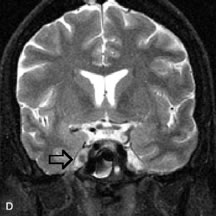

The MR angiography (MRA) technique uses fast gradient-echo scans to provide a noninvasive alternative for evaluating the carotid bifurcations and intracranial vessels. The time-of-flight MRA sequence is most commonly used and consists of a series of very thin, flow-sensitized, two-dimensional images that are acquired and subsequently reconstructed into a three-dimensional data set. The three-dimensional data can be rotated into any imaging plane by the computer software, providing images in multiple angiographic projections. MRA has recently become a fixture for noninvasive vascular imaging of the brain, face, and orbit. Advancements in spatial resolution and reduction in examination time has led to routine use of MRA for initial evaluation of vascular abnormalities such as aneurysms, arteriovenous malformations, and vascular tumors.25–27 The spatial resolution, however, remains inferior to that of conventional angiography. Angiography is still required for detection of aneurysms less than 2 to 3 mm since these are not reliably detected by MRA. Magnetic resonance venography (MRV) is considered the study of choice for evaluation of cerebrovascular veno-occlusive diseases, such as dural venous or cavernous sinus thrombosis.28